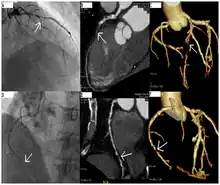

Angiography (left) and CT (middle and right) of chronic total occlusion lesions at the left anterior descending coronary artery (LAD) and right coronary artery (RCA).

CT angiography can act as a less invasive alternative to Catheter angiography. Instead of a catheter being inserted into a vein or artery, CT angiography involves only the injection of a CT-visible dye into the arm or hand via an IV line. CT angiography lowers the risk of arterial perforation and catheter site infection. It provides 3D images that can be studied on computer, and also allows measurement of heart ventricle size. Infarct area and arterial calcium can also be observed (however those require a somewhat higher radiation exposure). That said, one advantage retained by Catheter angiography is the ability of the physician to perform procedure such as balloon angioplasty or insertion of a stent to improve blood flow to the artery.[7]